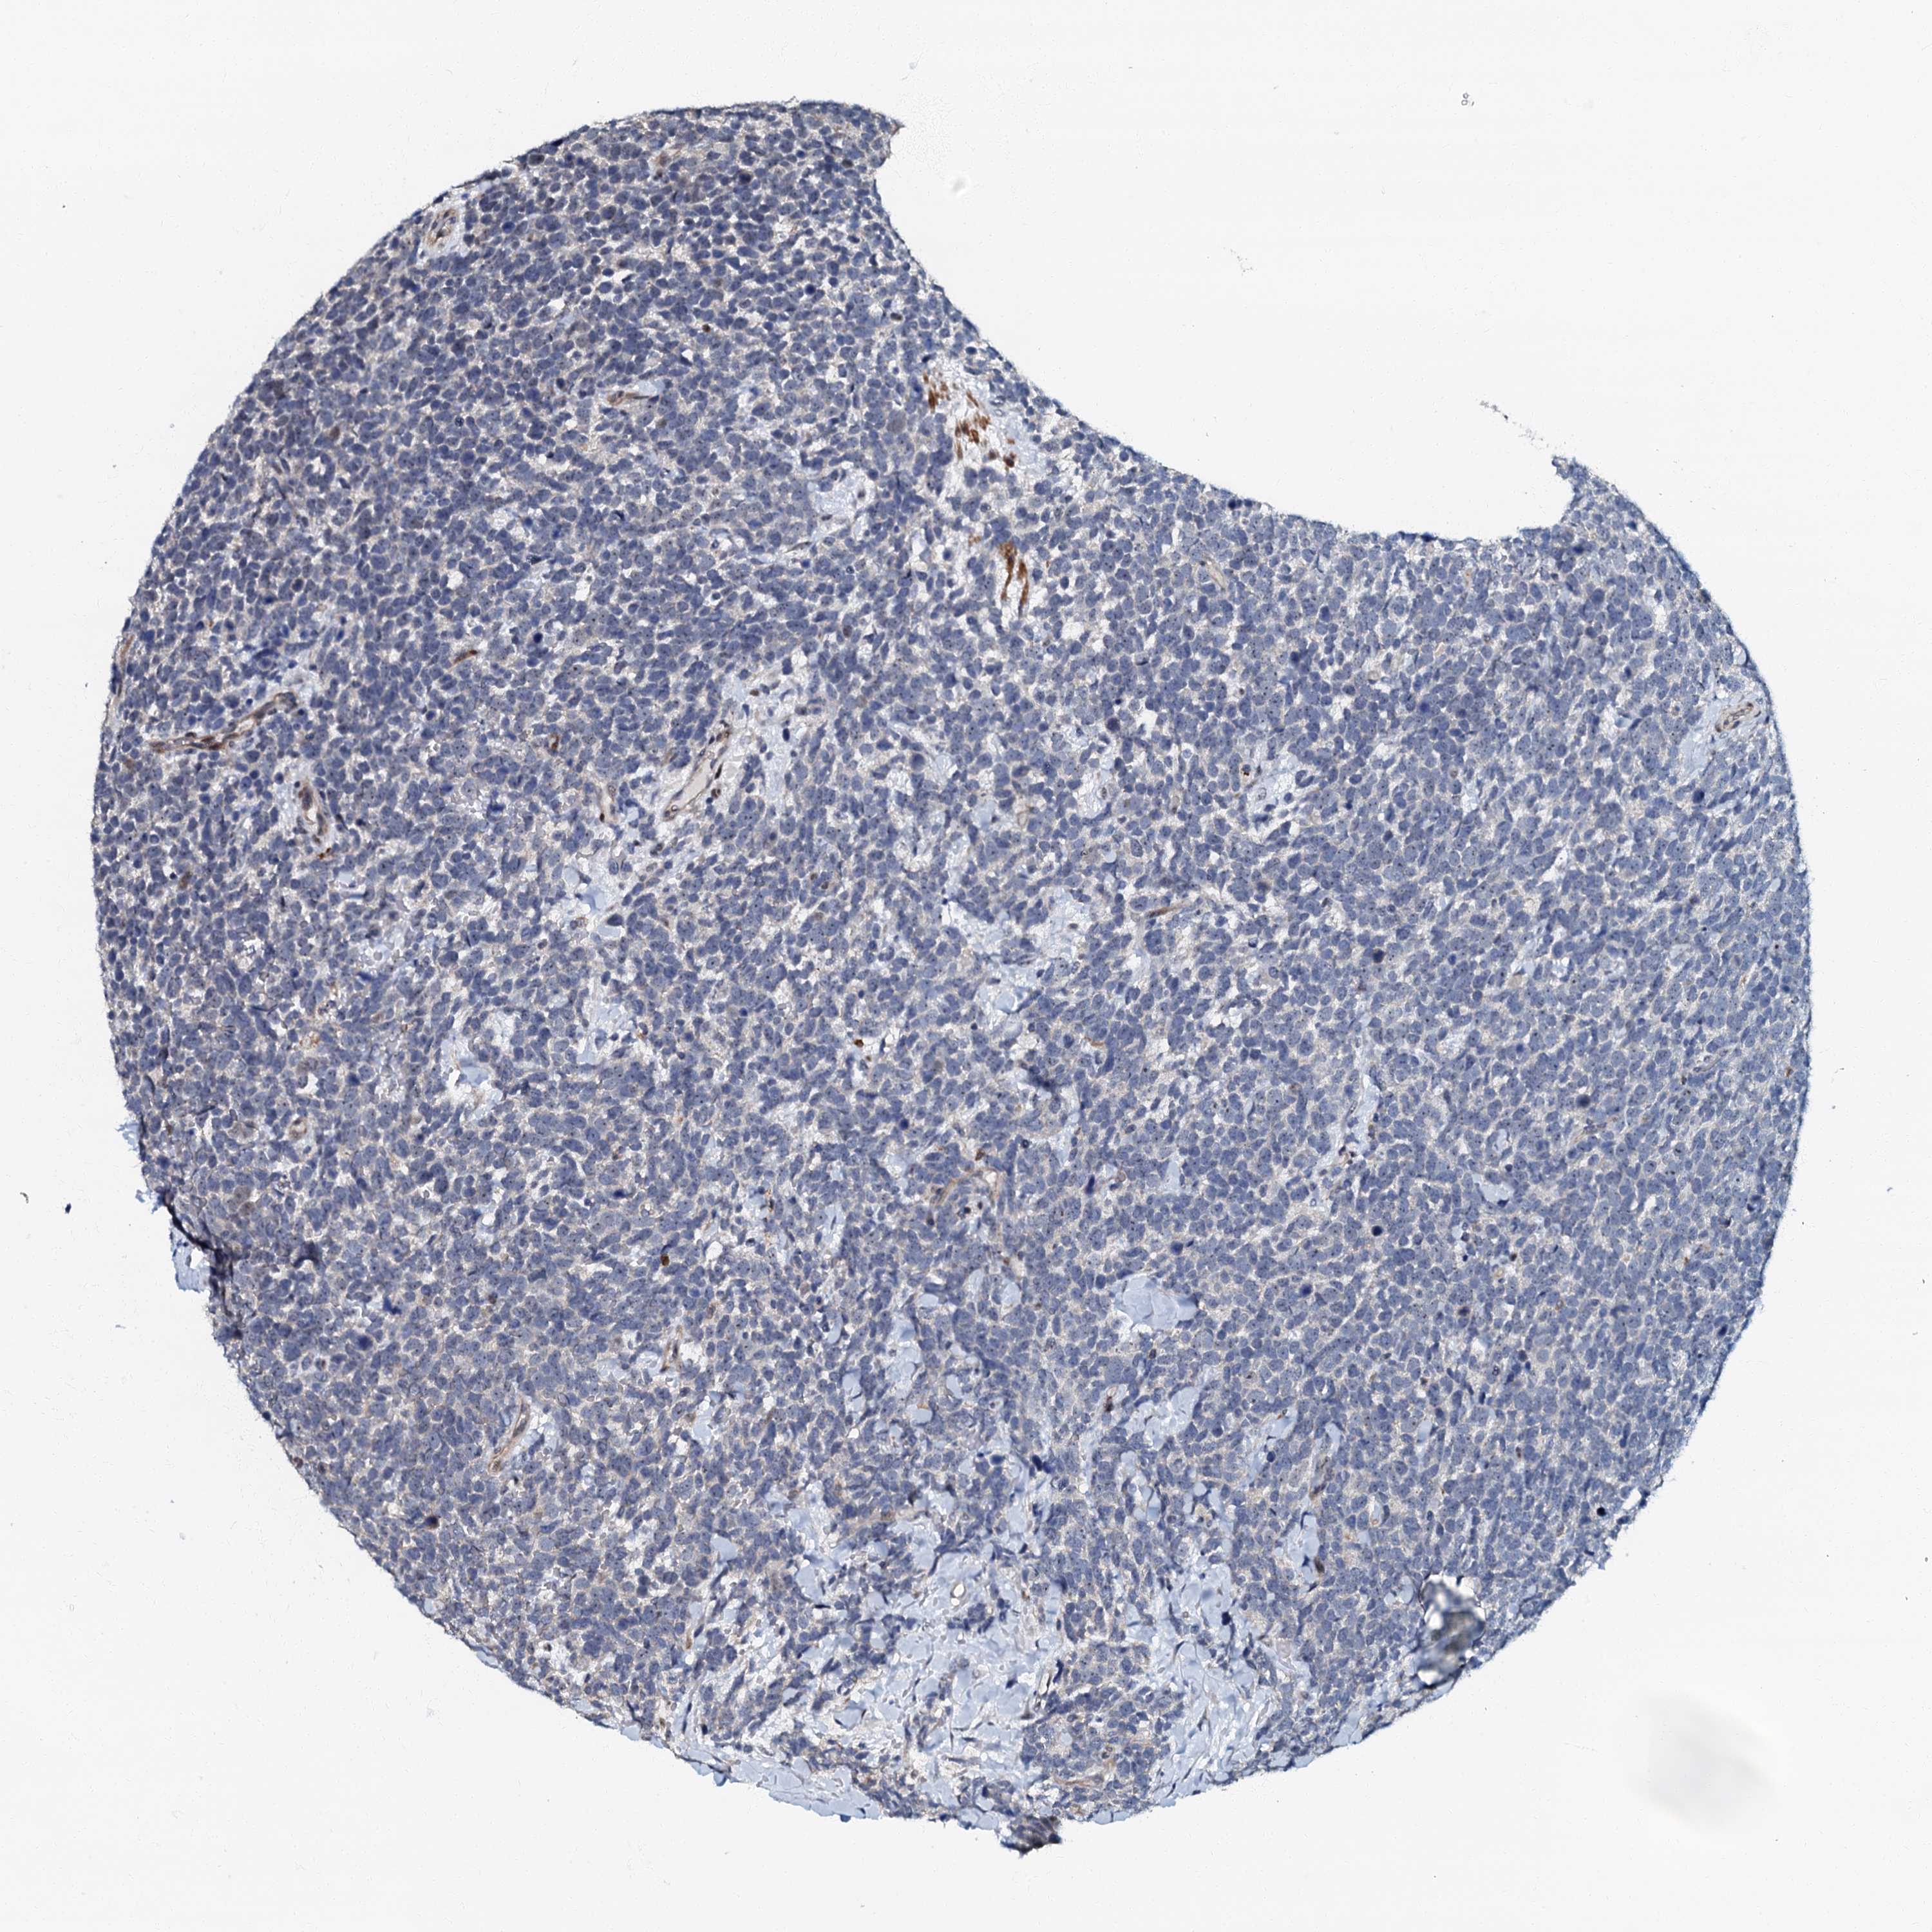

UROTHELIAL CANCER - Protein expressioni

A mouse-over function shows sample information and annotation data. Click on an image to view it in a full screen mode. Samples can be filtered based on level of antibody staining by selecting one or several of the following categories: high, medium, low and not detected. The assay and annotation is described here.

Antibody stainingi

Antibody staining in the annotated cell types in the current human tissue is reported as not detected, low, medium, or high, based on conventional immunohistochemistry profiling in selected tissues. This score is based on the combination of the staining intensity and fraction of stained cells.

Each image is clickable and will lead to virtual microscopy that enables deeper exploration of all samples and also displays staining intensity scores, fraction scores and subcellular localization as well as patient and tissue information for each sample.

Antibody HPA037947

Antibody HPA037948

Urothelial carcinoma, High grade

Urothelial carcinoma, Low grade

Urothelial carcinoma, NOS